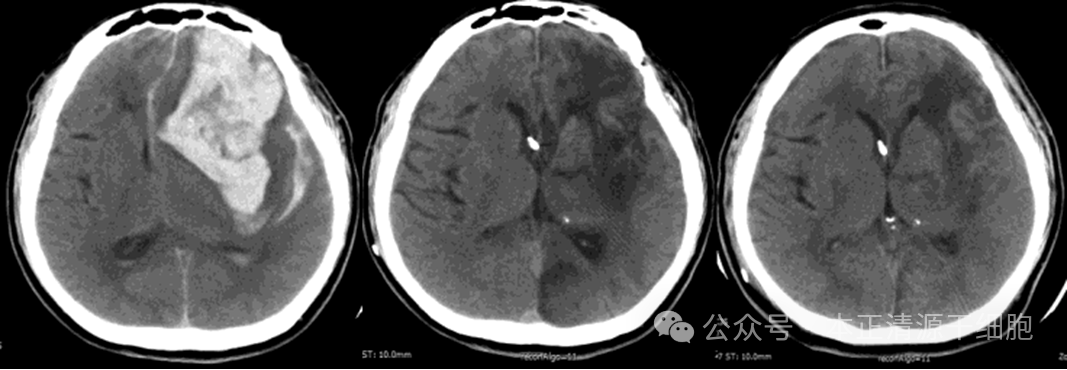

一例为51岁男性患者,有左额顶叶脑出血性卒中病史,患者也有高血压病史,以植物状态出院,并接受了气管切开术,采用鼻胃(NG)管喂养。在家庭护理期间,他的功能状态保持不变,没有明显的改善。

图片

然后,他的家人带着病人接受干细胞治疗。检查显示患者处于持续性植物人状态,国家卫生研究所卒中量表(NIHSS)评分23分,右偏瘫,患者气管切开并连接NG管。3周后,进行脑室部位间充质干细胞治疗,治疗后24小时的观察中未显示任何不良反应。随后患者回家,在1个月和2个月时,又进行了脑室部位的间充质干细胞治疗。

研究结果3个月、6个月和12个月的随访显示NIHSS评分有所改善(分别为20分、19分和19分),之前是23分。

在最后一次随访中,患者能够坐在轮椅上,取出气管切开术,不使用NG管进食,未发现其他副作用。

神经成像的发现,治疗后枕部梗死面积变化明显,治疗后血肿周围低密度面积减小。